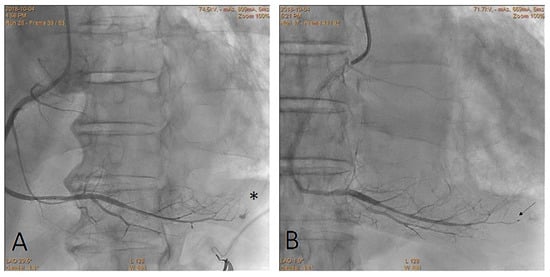

Embolization of Perforated Coronary Artery with a Fragment of Balloon Catheter (Cut Balloon Technique)—Multicenter Study

- Sobieszek, G.; Zięba, B. Balloon Fragment Technique Used to Close Distal Coronary Vessel Perforation. J. Invasive Cardiol. 2020, 32, E370–E372. [Google Scholar] [PubMed]

- Öcal, L.; Yılmaz, C.; Uysal, S.; Cerşit, S.; Zehir, R. Successful management of distal coronary artery perforation with the modified cut balloon technique during percutaneous coronary intervention. Anatol. J. Cardiol. 2022, 26, 66–68. [Google Scholar] [CrossRef] [PubMed]

- Alavi, S.H.; Hassanzadeh, M.; Dehghani, P.; Mehdipour Namdar, Z.; Aslani, A. A Novel Technique for Managing Guidewire-Induced Distal Coronary Perforation Using Coronary Balloon Pieces. JACC Case Rep. 2022, 4, 137–141. [Google Scholar] [CrossRef] [PubMed]

- Abdalwahab, A.; McQuillan, C.; Farag, M.; Egred, M. Novel economic treatment for coronary wire perforation: A case report. World J. Cardiol. 2021, 13, 177–182. [Google Scholar] [CrossRef] [PubMed]